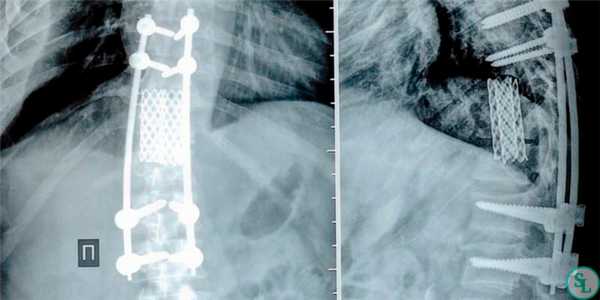

Также существуют отличия в методах фиксации позвонков при спондилодезе. При выборе переднего метода нейрохирург стабилизирует тела позвонков. Если же выбрана методика задней фиксации хирург работает с остистыми и поперечными отростками позвонков.

Но особенно результативным, по данным проведенных исследований, является межтеловой спондилодез. Поскольку тела позвонков значительно лучше снабжаются кровью, имеют большее количество клеточных элементов и отличаются высоким потенциалом к образованию новой костной ткани, имплантированные между ними объекты приживаются значительно лучше, чем установленные между отростками позвонков. При таком способе фиксации успешного спондилодеза удается добиться в 96% случаев. В противном случае позвонки могут не срастись, что приведет к сохранению болей в спине, а в дальнейшем к тяжелым последствиям.

Также может выполняться спондилодез через передне-боковой доступ. Показаниями к его проведению выступают серьезные травмы шейного отдела. В подобных случаях метод фиксации позвонков выбирается для каждого пациента индивидуально на основании результатов МРТ. Высокой эффективностью при оперативном лечении переломов шейного отдела позвоночника отличается межтеловой цервикоспондилодез, сопряженный с установкой передней фиксирующей пластины.

Чтобы иммобилизация позвоночно-двигательного сегмента была максимально надежной, нередко операция дополняется выполнением транспедикулярной фиксации. В таком случае устанавливаются специальные металлические конструкции, которые еще более упрочняют скрепление тел позвонков.